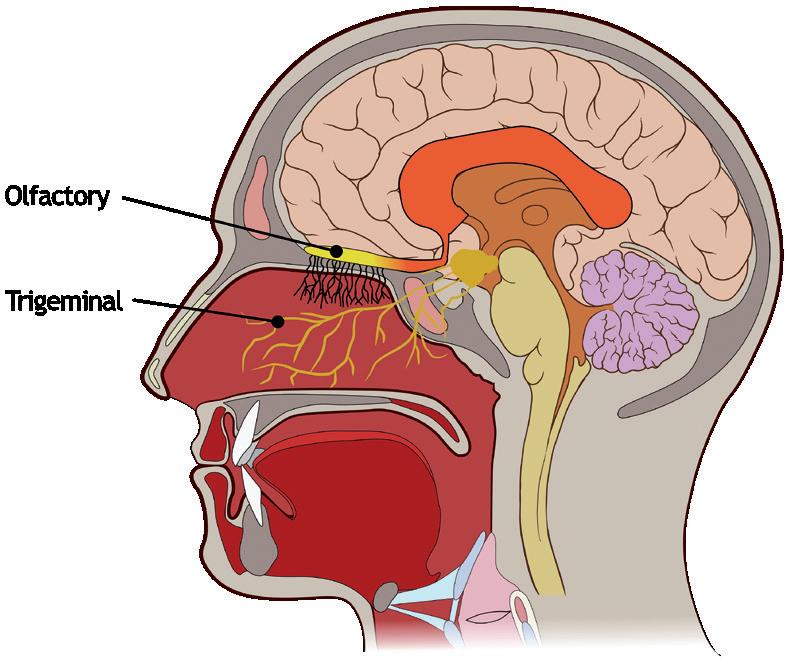

Addressing CNS Therapies Through Nose-to-Brain Pathways

Nemera

Interview – Exploring Nasal Casts in Nasal Drug Development

Julie Suman, Vice-President, Scientific Affairs

Aptar Pharma